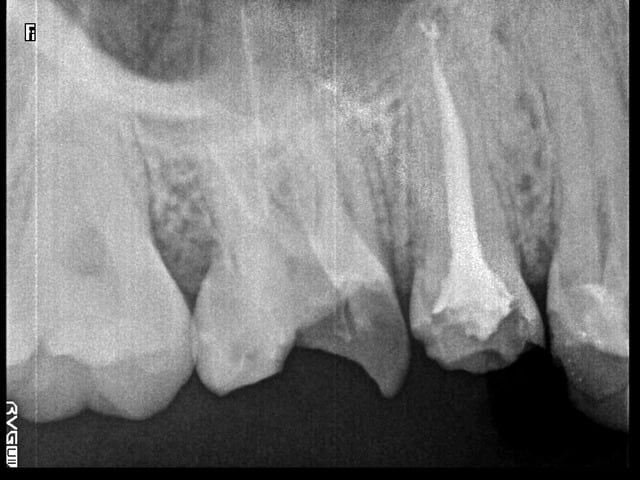

ps: ci-joint quelques exemples.

hello la compagnie , perso je trouve l'obturation mixte superbe et pratique( mais c la moins étanche les publications le confirment contrairement au touch n heat et Système B et Thermafil) les variation de technique tiennent de l'empirisme la technique initialement décrite parle de :

1-Maitre cône ISO

2-Condensation latérale au finger spreaders.

3-Deux ou 3 Cônes voir 4 dans las canaux larges .

4-Gutta condensor a LT -3 ou4 mm pour une bonne friction puis faire tourner au CA bleu.

5-Gardez le contacte avec la racine, laisser remonter et ça done de jolies obturations!.

Donc les "endos a ma sauce" sont des avis d'auteurs et peu reproductibles.